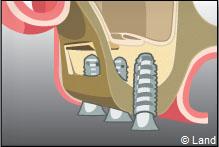

LES COMBLEMENTS SOUS-SINUSIENS

Ce comblement osseux est réalisé avant ou en même temps que la pose des implants.

L’intervention est réalisée sous anesthésie locale. Dans cet exemple le forage intéresse la paroi latérale du sinus.

Une fenêtre est délimitée et réclinée à l’intérieur du sinus de manière à aménager un espace. Cet espace est rempli par le matériau de comblement qui peut être recouvert par une membrane.

L’implant est posé dans la même séance ou 4 à 6 mois après la chirurgie de comblement.

Actuellement, tous les biomatériaux peuvent être utilisés pour les comblements sinusiens.

Après le comblement, il n’a jamais été décrit une quelconque perturbation de la physiologie sinusienne.